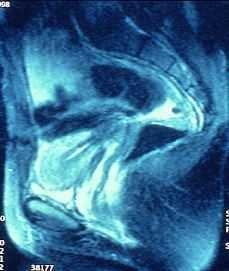

El estudio ecotomográfico del abdomen pélvico (mediante ecografía abdominal con repleción vesical, al tratarse de una joven sin relaciones sexuales previas), muestra un útero en anteversión con un diámetro longitudinal de 7,5 cm y un diámetro anteroposterior fúndico de 3,5 cm. Los cortes transversales muestran dos áreas correspondientes a endometrio divididas por un septo que llega a cérvix. En la cavidad izquierda se visualiza un moderado hematometra, lo que sugiere que se trata de una cavidad no comunicante (Fig. 2). Ambos ovarios presentan unas características tanto morfológicas como ecográficas normales. En la Resonancia Nuclear Magnética (RNM) se observa la presencia de dos hemicavidades uterinas separadas por un septo total. El hemiútero derecho presenta una morfología y cavidad conservadas, con un cérvix también de características normales. Sin embargo, el hemiútero izquierdo presenta una distensión de su cavidad, de señal hiperintensa tanto en las secuencias potenciadas en T1 como en las potenciadas en T2, compatible con hematometra. No se observa comunicación de la misma con el cérvix. Ambos ovarios presentan múltiples folículos con un tamaño y morfología dentro de los límites de la normalidad. El diagnóstico es de útero septo total con hemicavidad izquierda no comunicante, distendida por la presencia de hematometra (Figs. 3, 4 y 5). La vaginoscopia, mediante espéculo virginal, muestra un cuello uterino único con una única vagina. El examen histeroscópico muestra un canal endocervical normal que aboca directamente a una cavidad uterina de morfología tubular, en la que se visualiza un único orificio tubárico. Se resigue la pared media uterina sin visualizar ninguna comunicación con la otra cavidad. Se realiza un estudio ecográfico renal en que no se observan malformaciones a nivel del sistema urinario.

Figura 3. RNM (plano sagital). Hemicavidad izquierda distendida con señal hiperintensa que no comunica con canal cervical.

Figura 4. RNM (plano sagital). Hemicavidad derecha normal que comunica con canal cervical.